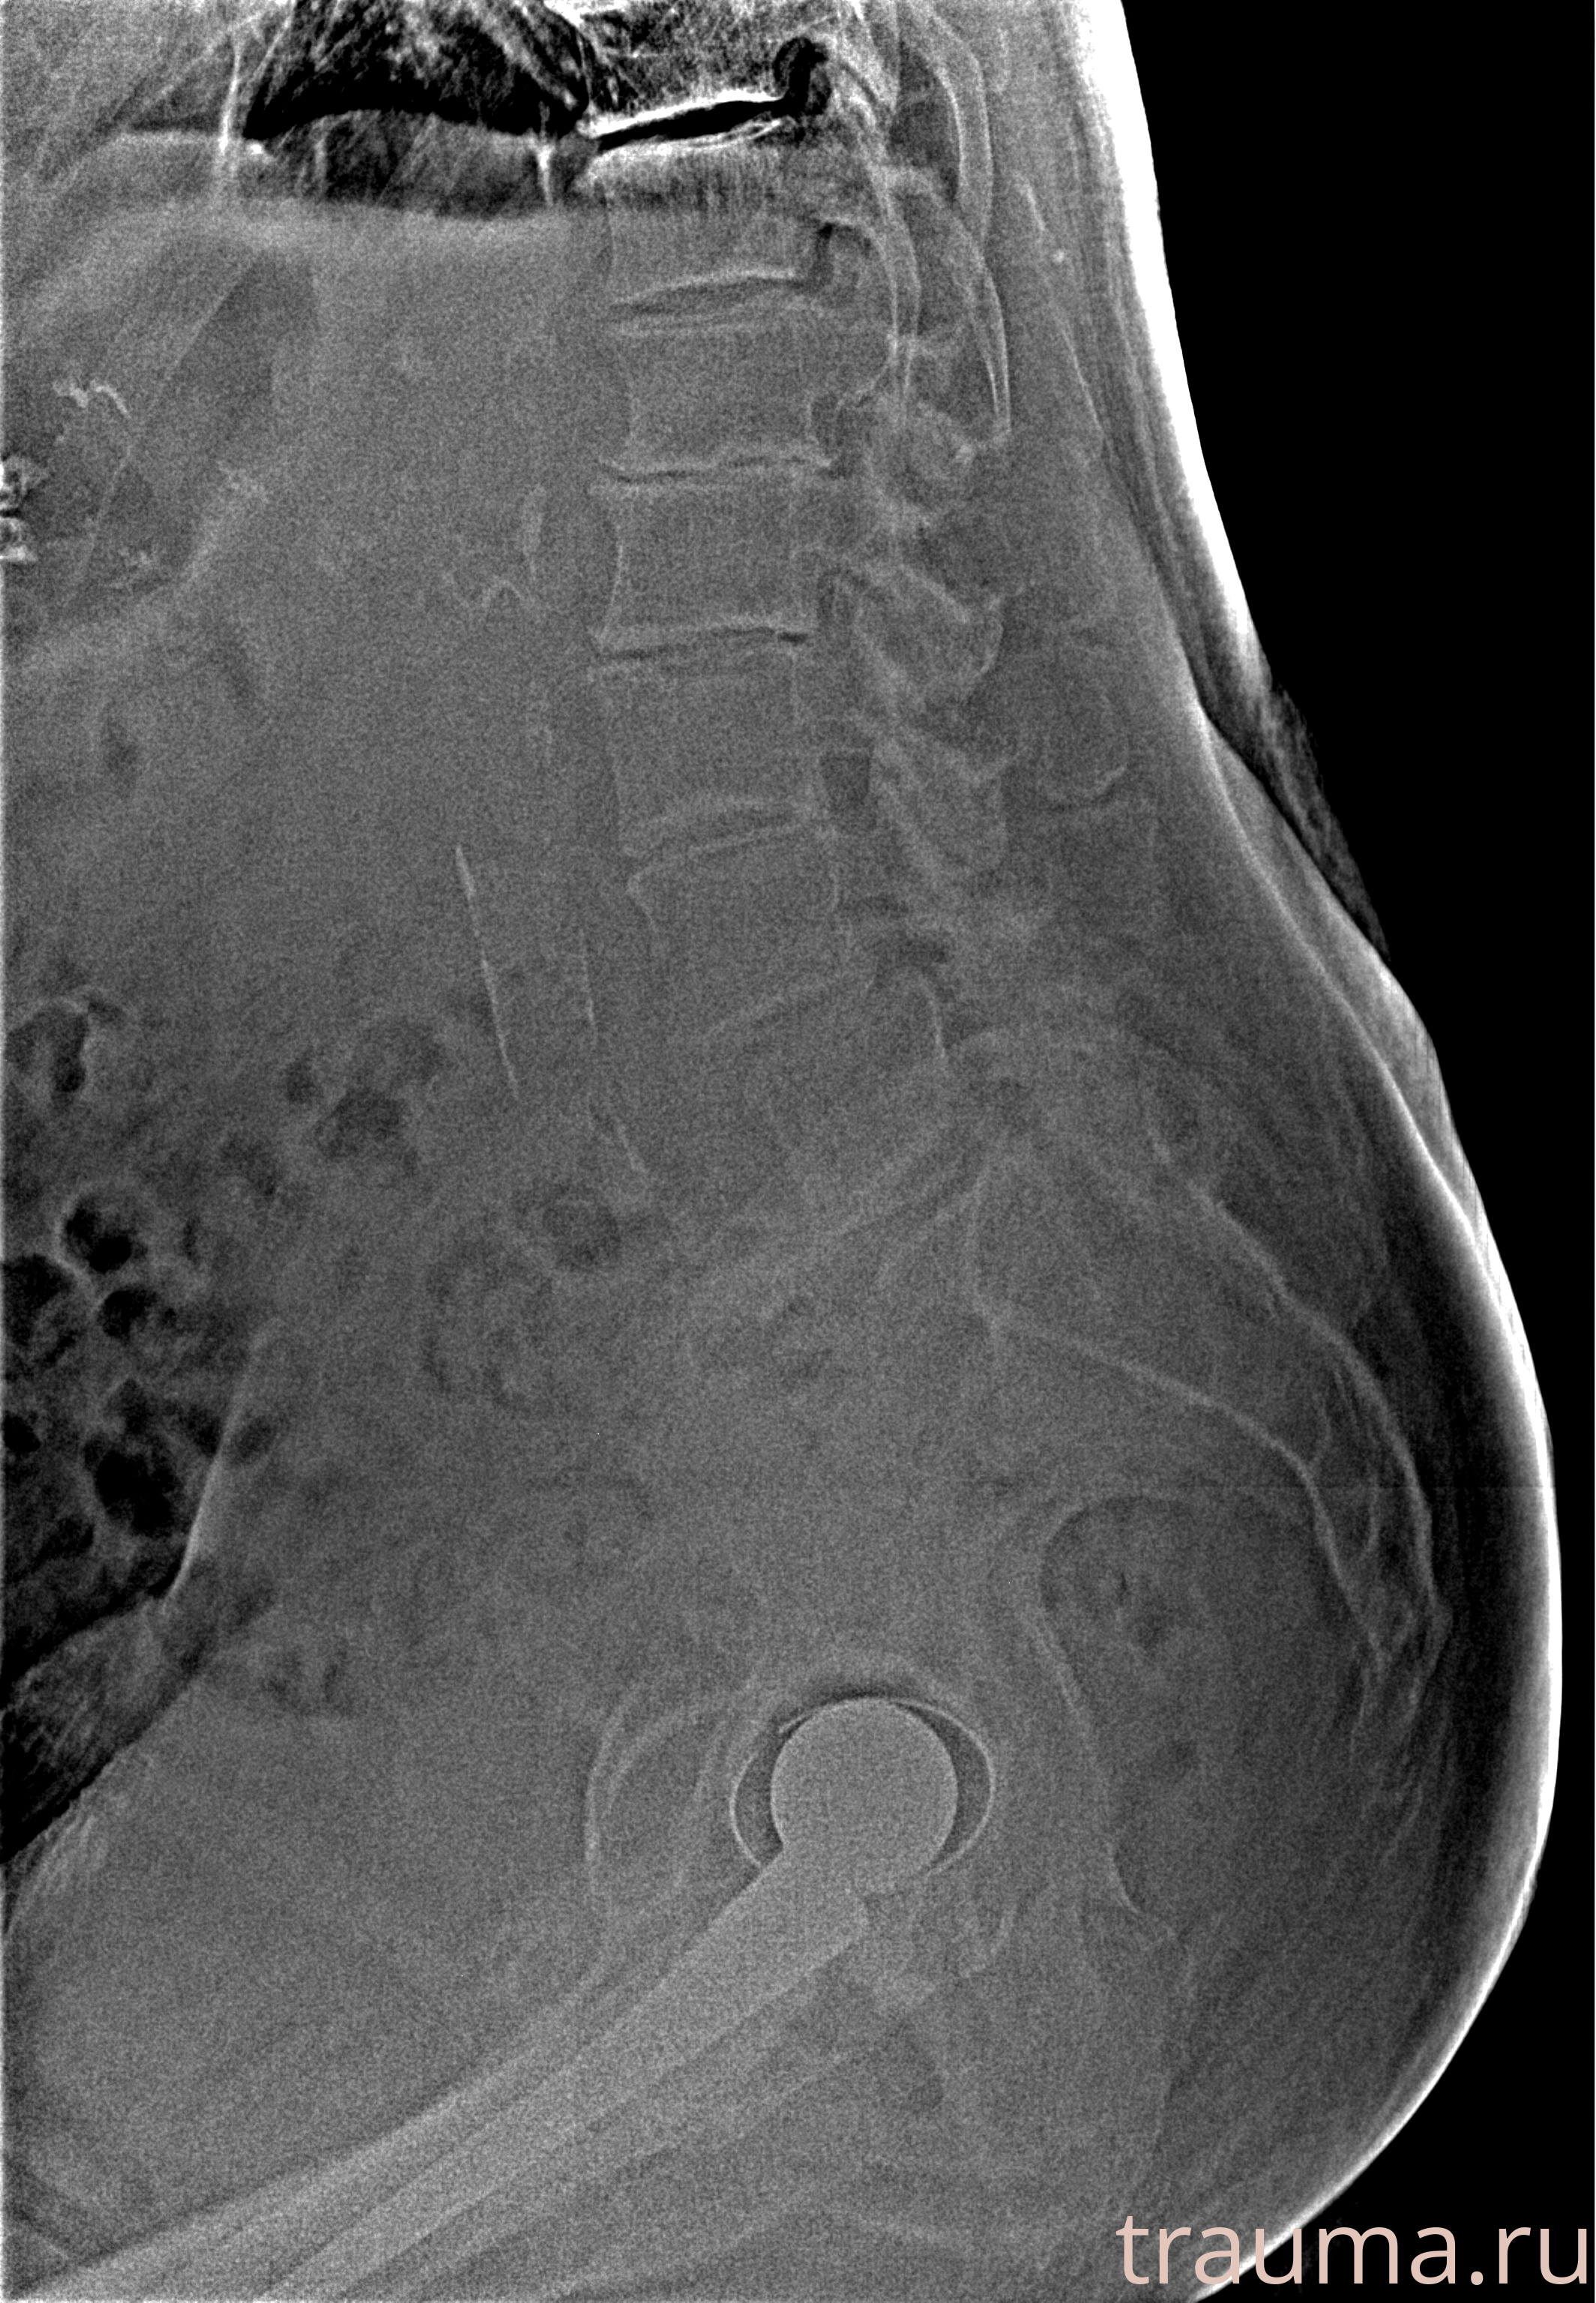

Рентген на дому: по вашему адресу приезжает врач-рентгенолог, травматолог-ортопед с мобильным рентгеновским аппаратом, проводит диагностику травмы или заболевания, делает необходимые рентгенограммы, дает рекомендации по дальнейшему лечению. Получить качественные снимки в домашних условиях возможно благодаря уникальной методике, разработанной МосРентген Центром для института  Склифосовского